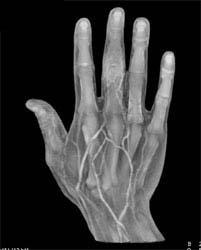

Diagnosis

Fracture/dislocation